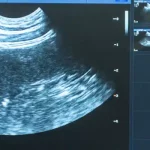

From routine blood tests and advanced imaging to specialist screenings, we offer a comprehensive range of diagnostic services designed to get a complete picture of your pet’s health. Every test is carefully analysed by our experienced team, and we take the time to explain the results in clear, straightforward terms. This approach ensures you fully understand your pet’s condition and the best steps to take, helping them stay happy, healthy, and comfortable.